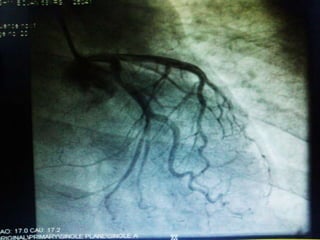

• Then patient was advised to get CAG done

CAG on 13th feb which showed Normal

Coronaries.

• Then patientwas advised to get CAG done shifted to ward on same day. • Patient was started on Inj VANCOMYCIN on 4th Feb under ICU Supervision. Patient tolerated antibiotics well then patient was advised to continue Inj Vancomycin and Inj Ceftriaxone on OPD basis. Central Line Insertion was done on 6th Feb, Patient was discharged with central line in situ on 6th Feb and was explained about the need of MVR once the infection settles .

• 19.

• Patient cameback on 10th feb and undergone CAG on 13th feb which showed Normal Coronaries. • Patient underwent MVR with 27mm BiOCAR VALVE ON 17th Feb. • Post op Echo done on 10th march showed